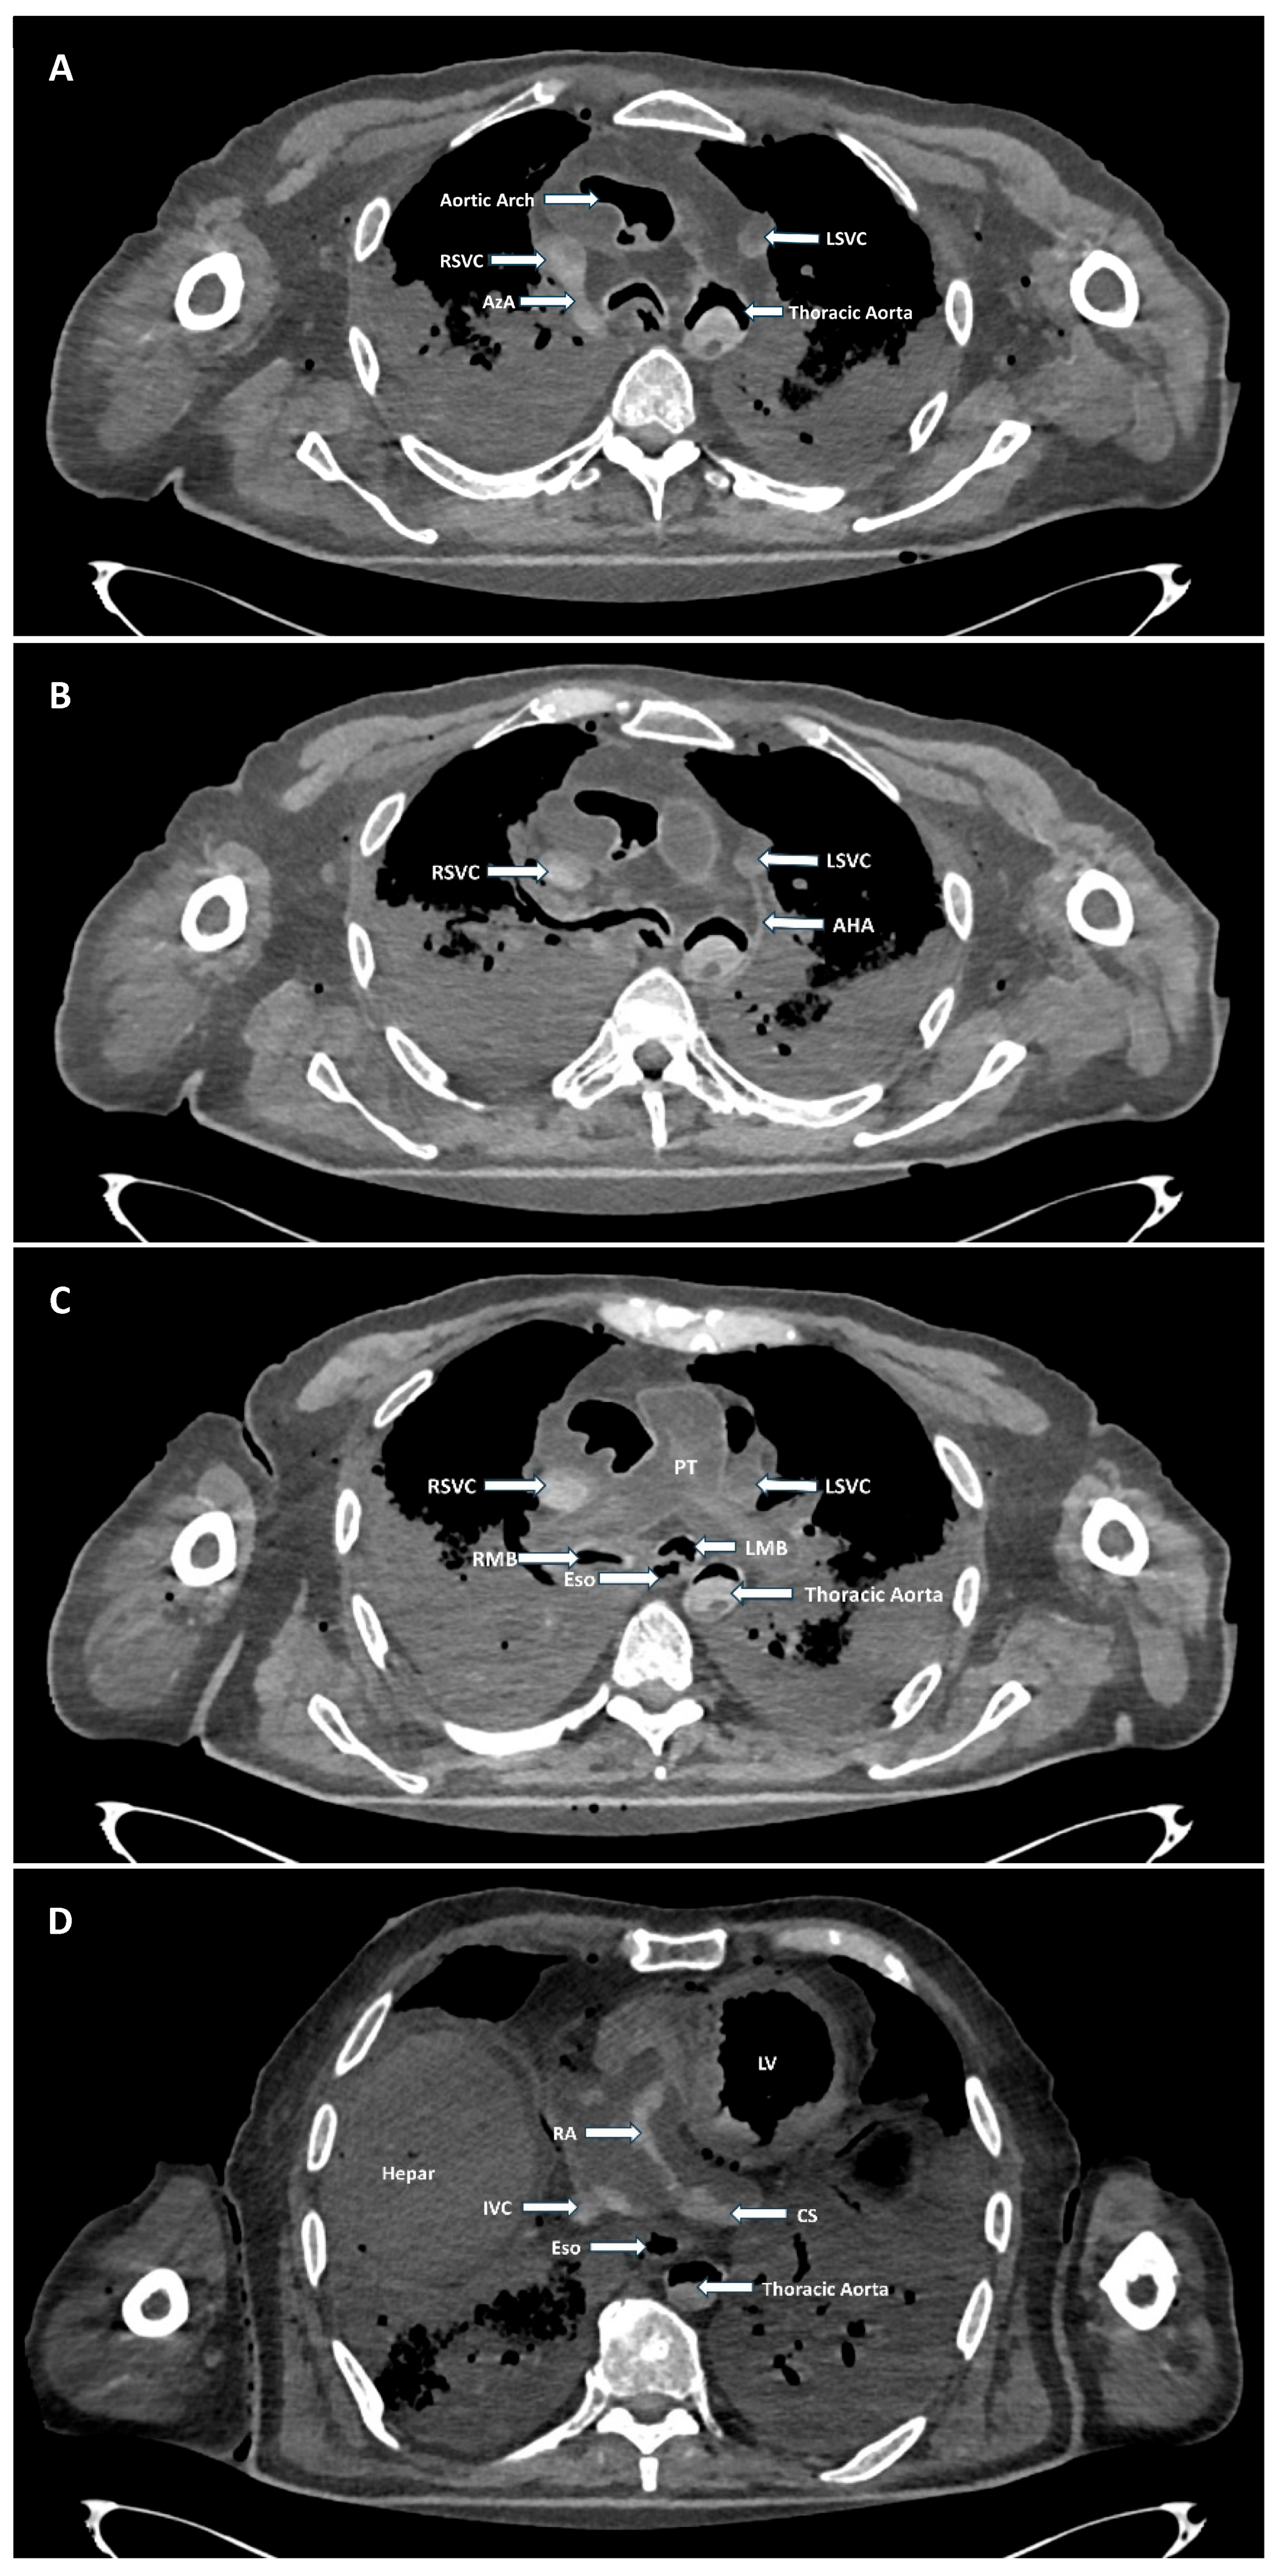

A Case of Double Superior Vena Cava with a Rare Accessory Hemiazygos Arch Crossing over the Descending Aorta in a Male Body Donor

3. Findings